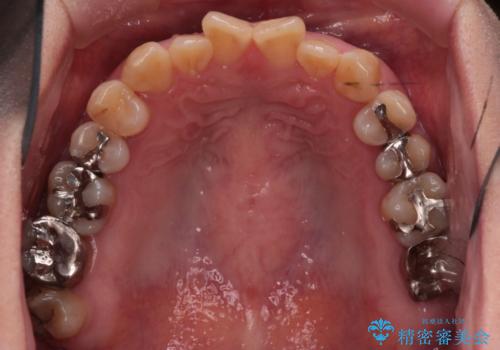

- 上の前歯の捻れと、前歯で物が噛めないことを主訴に来院されました。

前歯の翼状捻転とオープンバイト傾向だったため、インビザラインにて矯正を行いました。右下の奥歯は保存不可だったため、抜歯を行いインプラントにて修復を行なっています。

翼状捻転はインビザラインでは苦手とする動きですが、ここまで綺麗に治すことができました。